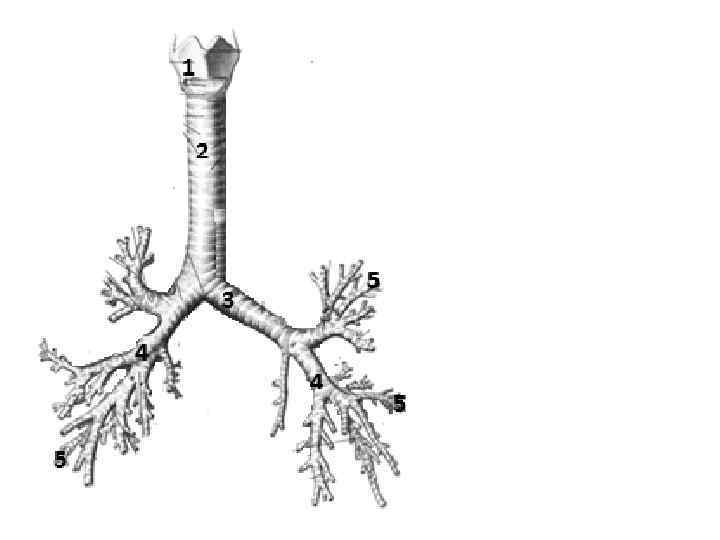

Трахея на нижнем конце делится на 2 ветви, образуя главные бронхи, которые входят в состав корней легких. Главными бронхами начинается бронхиальное дерево. Оно подразделяется на внелегочную и внутрилегочную часть.

Бронхиальное дерево: → долевые → внелегочные зональные бронхи → 10 правый и левый главные бронхи внутрилегочных сегментарных бронхов (бронхи крупного калибра) → субсегментарные бронхиолы (бронхи среднего калибра) → внутридольковые калибра) → междольковые бронхи (бронхи → терминальные бронхиолы малого